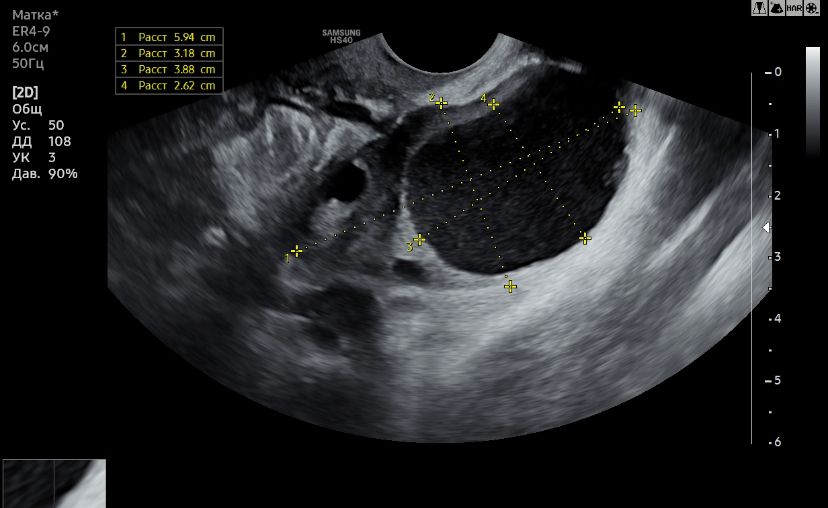

Ну похоже, что у вас в одном зреет доминантный фолликул, а в другом киста желтого тела, а с эндометрием что? Какой он толщины? Какой день цикла? В правом очень уж большое образование, поэтому она и предположила кисту под вопросом. Вводных данных очень мало, врач не смотрит только по размеру образований в яичнике, важен размер эндометрия еще и наличие или отсутствие жидкости, тогда можно понять, что на картинке. А так пальцем в небо. Полностью прикладывайте весь результат узи на будущее

Виктория, эндометрий 8 мм, но за три дня до этого Узи был 10-11мм. День цикла тут 27, но у меня он не стабильный, + я сейчас на дюфе, и овуляция пришла на 8 день приема этих таблеток и на 24 дц. Все очень загадочно дня меня)

Это фолликула

Алена , если у Вас в обоих яичниках жёлтое тело, значит в один цикл вышли две яйцеклетки.

Жёлтое тело

Mira, есть, это левый яичник, есть еще один снимок правого яичника(прикреплю) вот в нем сказали киста желтого тела 🫠 Изображение

Mira, получается два желтых тела в двух яичниках?)

Алена , нет совсем. Киста-это то,что могло остаться ещё с прошлого-позапрошлого цикла. Но она могла появиться и в этом месяц.

Mira, Появилась в этом цикле, буквально на зри дня, сразу после овуляции)